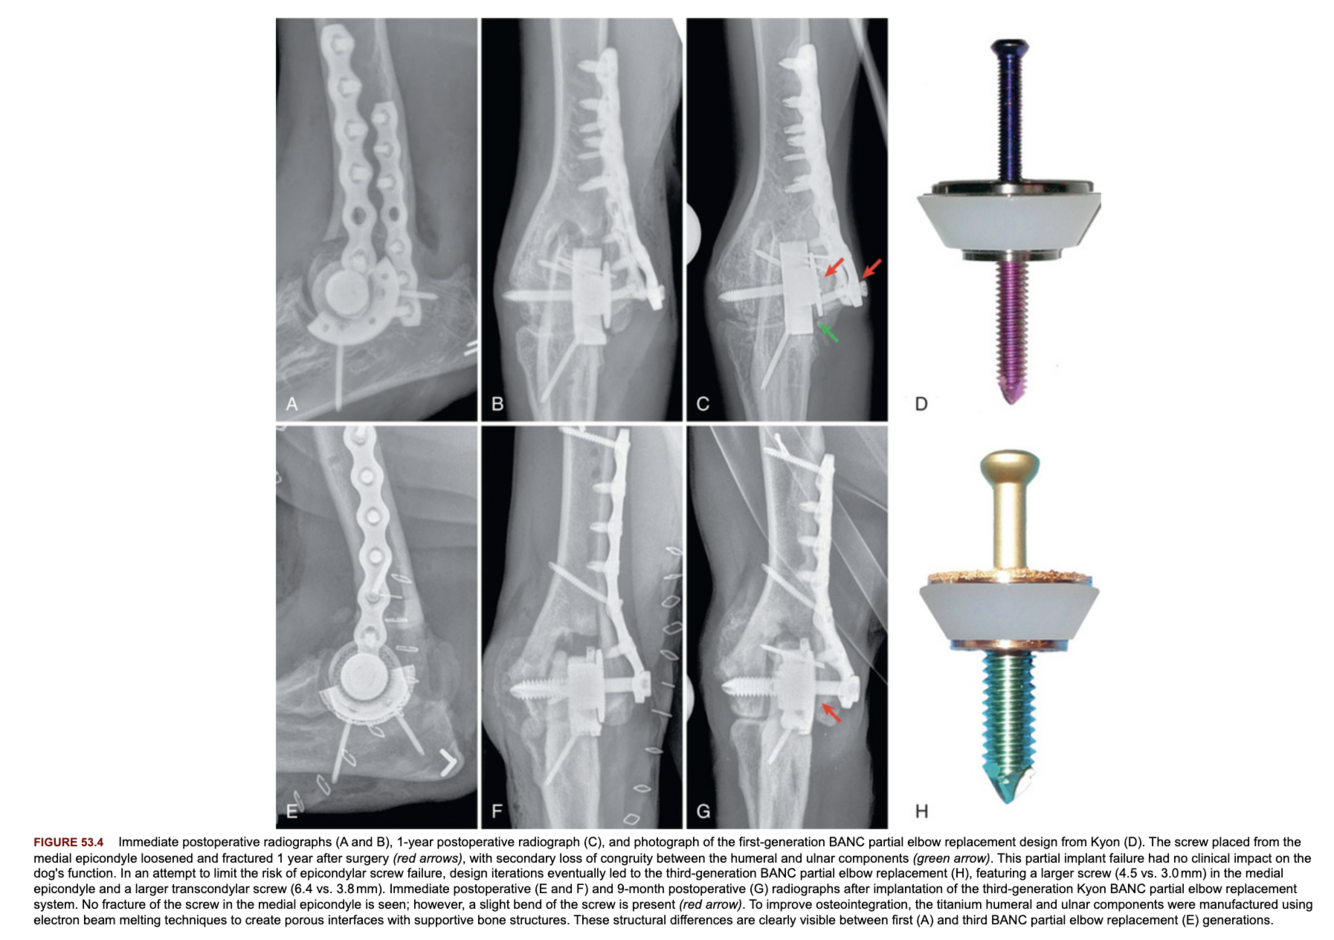

What are the components of the BANC total elbow replacement system?

What were the changes made to the second generation BANC total elbow replacement system?

Larger transcondylar and medial epicondylar screw to prevent failure, and electron beam melting of the titanium components to improve osseointegration.